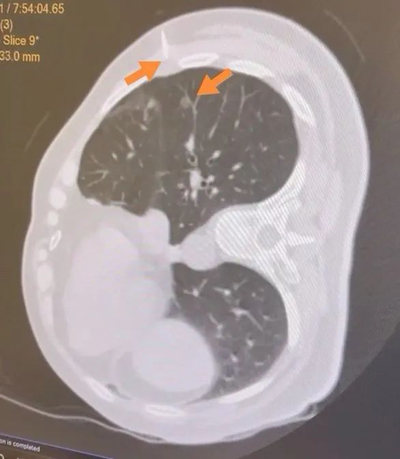

手术之前首先进行CT引导下经皮肺穿刺定位,在CT引导下将定位针放置在肺结节旁边。但是因为结节较小,而且紧贴靠肺动脉分支,穿刺过程中极容易引起肺内血肿,肺内出血更会加剧寻找结节的难度。在放射科的帮助下,我们通过术前CT定位,将穿刺针放置在结节下方约2cm左右的位置,术中根据定位针的位置在其下方行经胸腔镜肺楔形切除手术,不仅能够保证完整切除结节,且切缘距肿瘤能够保证有足够的距离。

上方箭头所指即为穿刺定位针进针位置;下方箭头所指为肿瘤位置。